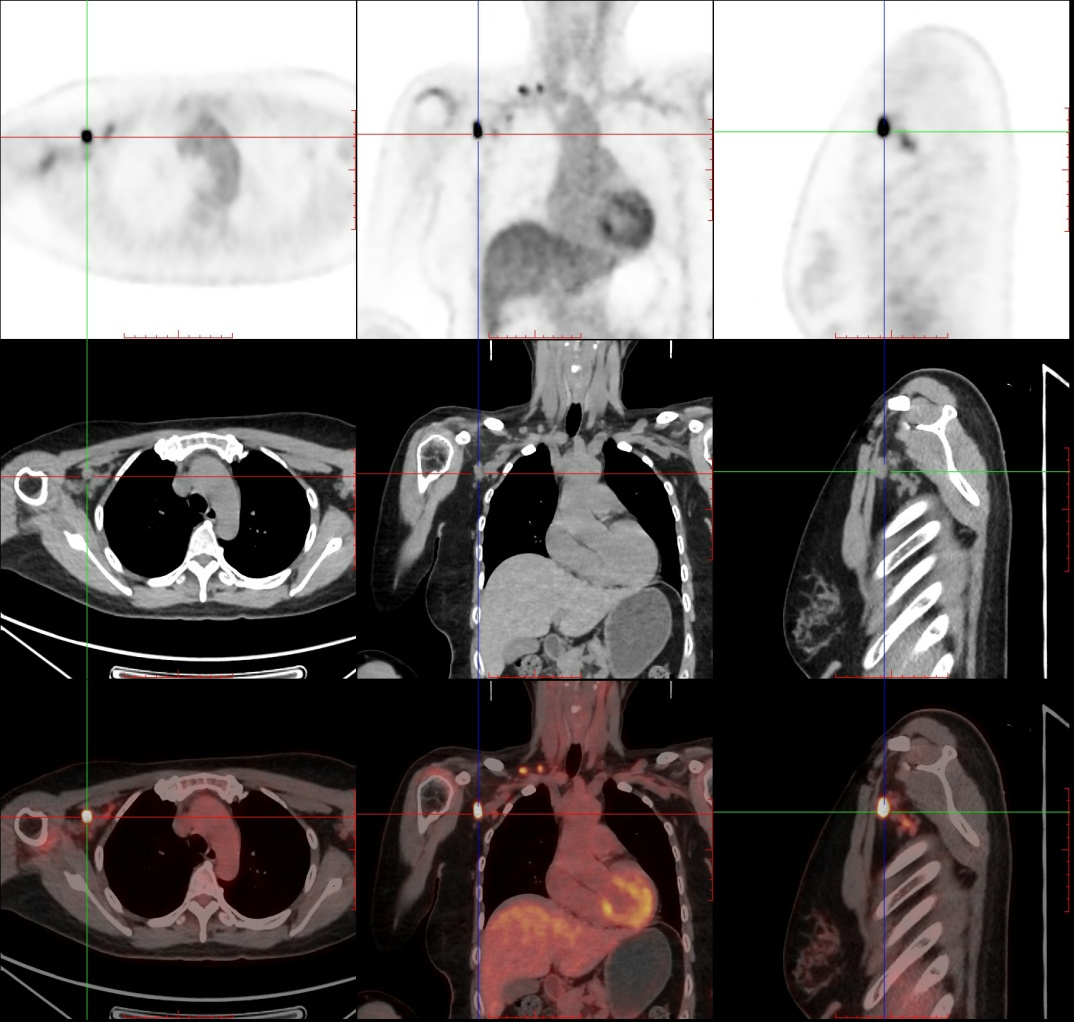

上图示右侧腋窝及右侧锁骨上区可见不等大小的淋巴结,FDG药物摄取增高,提示淋巴结转移。

上图示右上臂内侧术后改变,术区可见FDG药物摄取不均匀增高,提示手术未切除干净,肿瘤有残留。 上图示右侧腋窝及右侧锁骨上区可见不等大小的淋巴结,FDG药物摄取增高,提示淋巴结转移。